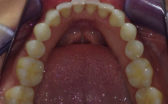

Whilst being fairly happy with my smile, I have always wanted to have perfectly straight upper and lower front teeth. There was some overlap of my upper lateral incisors (the teeth next to the front teeth) over my front teeth. My lower front teeth overlapped each other and were a bit crowded. I did not want to have a long course of braces to correct this, so Cfast sounded like a good option for me.

- Before

- After